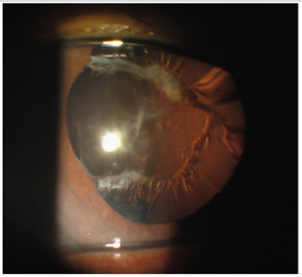

A 72-year-old male was a victim in an accident 3 years ago and rupture of eyeball with traumatic cataract was noted on the left eye at that time. He was admitted at a medical center where the primary repair of corneal perforation wound and lensectomy were performed but no intraocular lens was implanted concomitantly in this emergent management. This patient came to our clinic and asked for further evaluation 3 years later. A detailed work-up was carried out at our clinic, which included uncorrected visual acuity (UCVA), best corrected visual acuity (BCVA), autorefractometry, non-contact tonometry, corneal topography, slit lamp bio microscopy and indirect ophthalmoscopy. The uncorrected visual acuity was 20/100 and 20/2000 on the right and left eyes respectively. With a subjective refraction of -1.00 -2.5 x 95OD and +12.00 -0.75 x 100OS, the best-corrected visual acuity was 20/50 on the right and 20/100 on the left side respectively. For the left eye, slit lamp bio microscopy showed a whitish scar about 1 mm away from the center of cornea nasally (Figure 1). The anterior chamber depth was not shallow, but the pupil was irregular shaped and mid-dilated. There was a posterior synechia between the iris and the residual lens capsule around the nasal part of the pupil, but no implantation of intraocular lens was noted (Figure 2). Dilated fundus examination was unremarkable for each eye which ruled out the existence of active fundus pathology, such as retinal detachment, retinal hemorrhage, cystoid macular edema, macular hole and other active retinopathies.

Figure 2: There was a posterior synechiae between the iris and the residual lens capsule around the nasal part of the pupil, but no implantation of intraocular lens was noted.